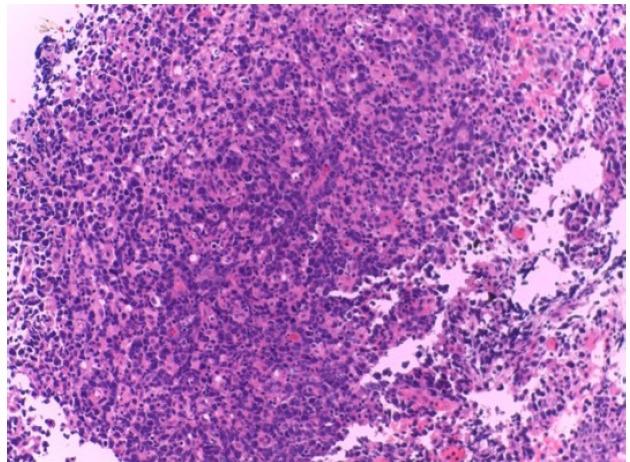

Primary lymphoma originating from the lacrimal drainage system is a rare disease. Such lymphomas are mostly B-cell in origin and present nonspecific symptoms. The treatment of malignant lymphoma of the lacrimal drainage system is slightly different. We present the case of a 71-year-old woman with a painless mass below the medial canthus. Computed tomography (CT) scan of the orbit revealed a mass invading the right lacrimal sac. An incision biopsy was obtained, and the pathologic findings suggested a diagnosis of primary diffuse large B-cell lymphoma of the lacrimal sac. The patient was treated with chemotherapy and intrathecal methotrexate. After completing eight cycles of chemotherapy, the patient was followed up by a CT scan, which revealed nearly total resolution of an ill-defined enhancing mass. At the time of this case report writing, the patient is in complete remission at six months with no other complications.